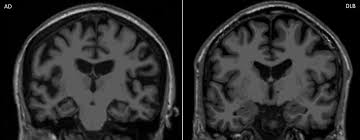

Lewy, the scientist who discovered them. Loss of substantia nigra hyperintensity on 7 tesla mri of parkinson's disease, multiple system atrophy, and progressive supranuclear palsy. Besides nuclear imaging methods, the clinical utility of structural neuroimaging with magnetic resonance imaging (mri) for differential comparison between dementia with lewy bodies and alzheimer's disease. You also might see things that aren't there, called hallucinations. Lbd is a term that covers two conditions that have similar. Protein deposits, called lewy bodies, develop in nerve cells in the brain regions involved in thinking, memory and movement (motor control). Certain nuclear scans of the brain, including positron emission. How is lewy body dementia (ldb) diagnosed? Dr michael firbank discusses his study using functional mri in lewy body dementia and alzheimer's disease at the newcastle university institute. Focal atrophy in dementia with lewy bodies on mri: Memory loss is not always an early symptom. Lewy body dementia (lbd) is a type of progressive dementia. Many people also experience changes in alertness including daytime sleepiness, confusion or staring spells.

Differences In Mr Features Of The Substantia Innominata Between Dementia With Lewy Bodies And Alzheimer S Disease Semantic Scholar

Differences In Mr Features Of The Substantia Innominata Between Dementia With Lewy Bodies And Alzheimer S Disease Semantic Scholar from d3i71xaburhd42.cloudfront.net

By this point, most caregivers are worried that something is seriously wrong and seek medical attention. These deposits, called lewy bodies, affect chemicals in the brain whose changes, in turn, can lead to problems with thinking, movement, behavior, and mood. Many people also experience changes in alertness including daytime sleepiness, confusion or staring spells. In lbd, protein deposits build up in the brain. Lewy body dementia (lbd) is a type of progressive dementia that leads to a decline in thinking, reasoning and independent function because. Dementia with lewy bodies or lewy body dementia is dementia caused by the presence of lewy bodies in the brain. Lewy body dementia (lbd) is often regarded as the second most common dementia in older individuals after alzheimer disease,1,2 possibly sharing the. Memory loss is not always an early symptom. How is lewy body dementia (ldb) diagnosed? Lewy body dementia symptoms include recent loss of memory, difficulty concentrating or paying attention, misperceptions of space and time. The deposits are called lewy bodies and are named after friedrich h. Mri can show loss of brain cells (atrophy), but this occurs with other types of dementia too. Protein deposits, called lewy bodies, develop in nerve cells in the brain regions involved in thinking, memory and movement (motor control).